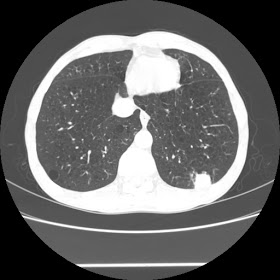

A 52 Years old man suffering with chest pain since 3 years

For seen patient record file please click here

HRCT Chest